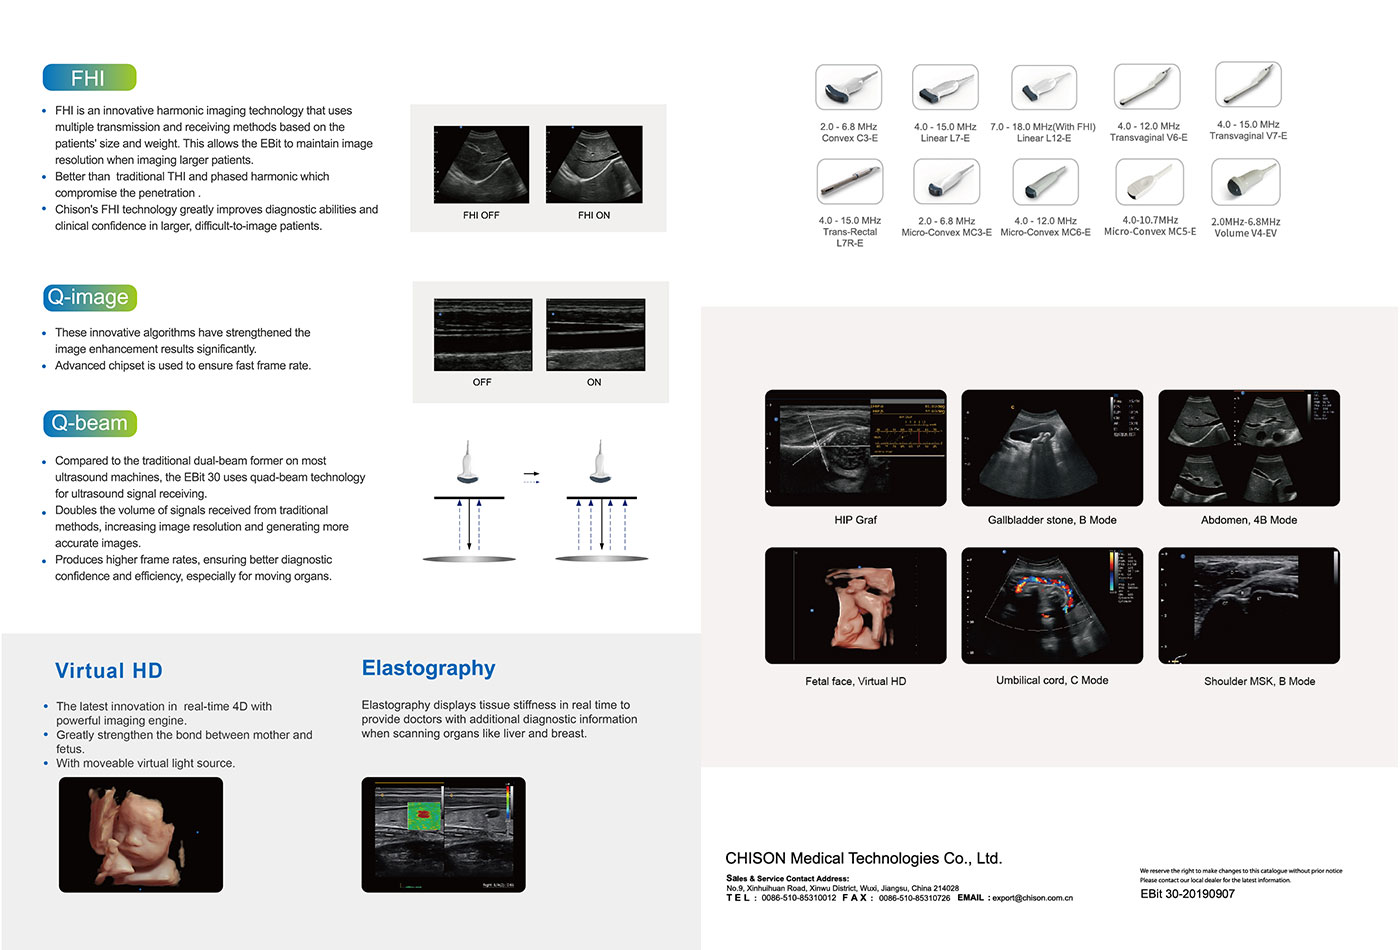

●FHI is an innovative harmonic imaging technology that uses multiple transmission and receiving methods based on the

patients' size and weight. This allows the EBit to maintain image resolution when imaging larger patients.

●Better than traditional THI and phased harmonic which compromise the penetration。

●Chison's FHI technology greatly improves diagnostic abilties and clinical confdence in larger, difficult-to-image patients.

●These innovative algorithms have strengthened the image enhancement results significanty.

●Advanced chipset is used to ensure fast frame rate.

●Compared to the tradtional dual-beam former on most ultrasound machines. the EBit 30 uses quad-beam technology for utrasound signal receiving.

●Doubles the volume of signals received from traditional methods, increasing image resolution and generating more accurate images.

●Produces higher frame rates, ensuring better diagnostic confidence and eficiency, especially for moving organs.

●The latest innovation in real-time 4D with

powerful imaging engine.

●Greatly strengthen the bond between mother and fetus.

●With moveable virtual light source.

Elastography displays tissue siffness in real time to provide doctors with additional diagnostic information when scanning organs like liver and breast.